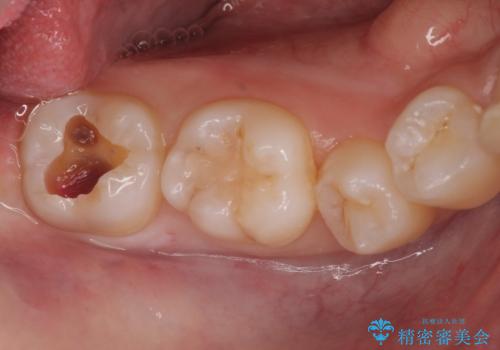

ご希望に沿って、ゴールドインレーにて治療を行いました。

- PGA(ゴールド)インレー 6.6万円 × 2本費用は治療当時の料金となります

ゴールドインレーは適合がよく、強度もあり、腐食もしにくく、アレルギーのリスクが極めて少ない安定した治療法です。虫歯の再発リスクを減らすことができます。